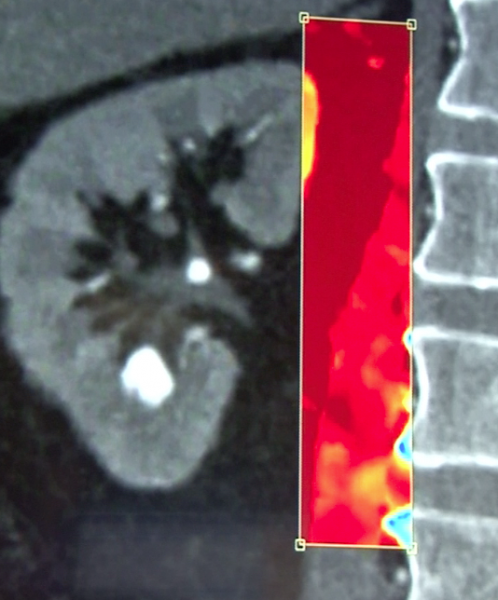

Philip's spectral CT showing how the system can identify the atomic number of iodine and calcium from photons on the scan and overlay a color map showing the chemical composition of materials in the body. This image shows a traditional grayscale Hounsfield image of a vessel and the right image showing a spectral version showing color-coded iodine and calcium.

Using a type of spectral analysis, the system can separate out materials made up of specific atomic numbers off the periodic chart of elements. The system so far has been tested for iodine and calcium. This can be used to help differentiate between areas of high blood contrast uptake and calcified areas, which can be useful in diagnosing kidney stones and better delineating various types of atherosclerotic plaque in arteries. Elements can be assigned specific color codes to make them standout on scans, even if the surrounding tissue has similar Hounsfield unit numbers.